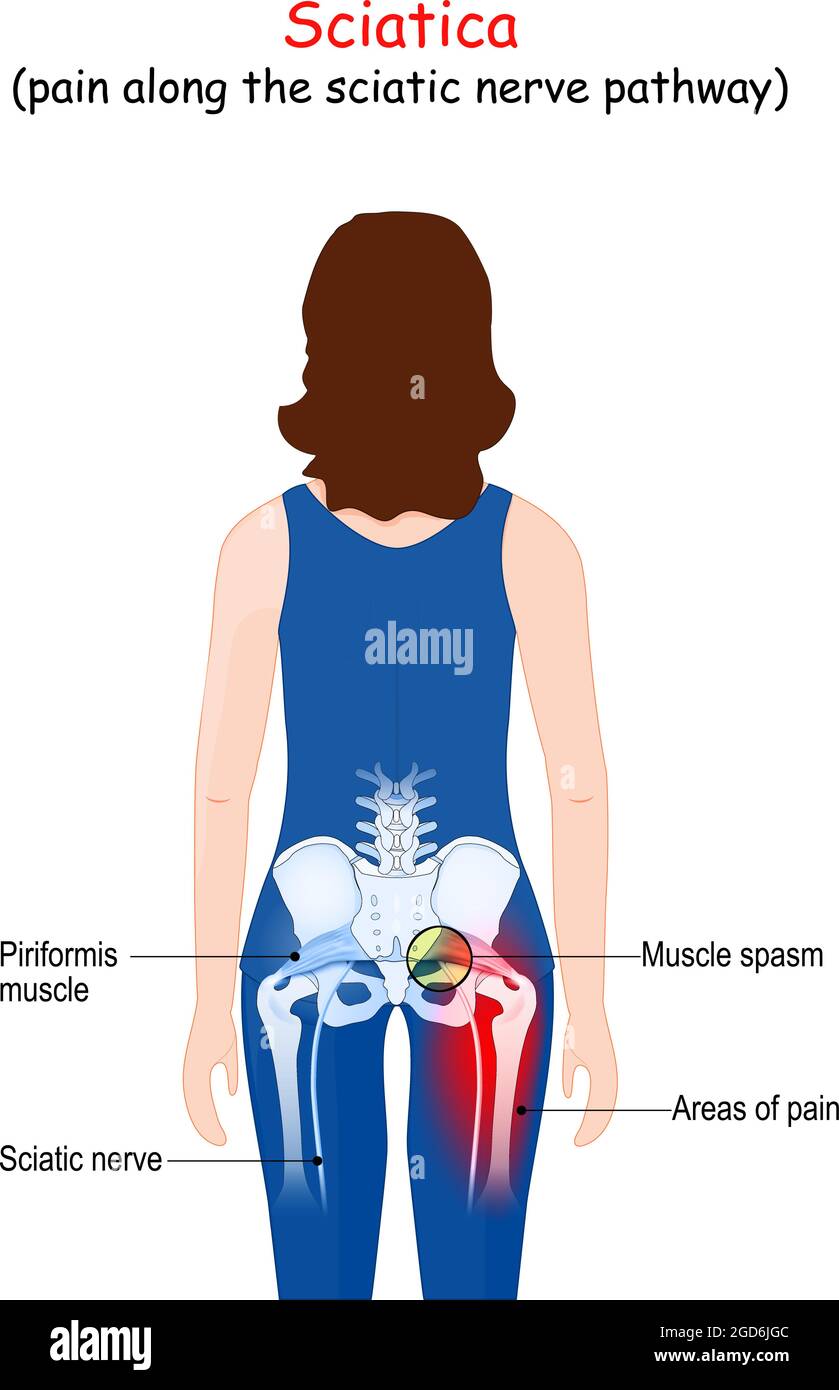

Sciatique. Douleur le long de la voie du nerf sciatique du bas du dos à travers les hanches à la jambe. Corps d'un patient (femme) avec des zones de douleur du dos Illustration de Vecteurhttps://www.alamyimages.fr/image-license-details/?v=1https://www.alamyimages.fr/sciatique-douleur-le-long-de-la-voie-du-nerf-sciatique-du-bas-du-dos-a-travers-les-hanches-a-la-jambe-corps-d-un-patient-femme-avec-des-zones-de-douleur-du-dos-image438396012.html

Sciatique. Douleur le long de la voie du nerf sciatique du bas du dos à travers les hanches à la jambe. Corps d'un patient (femme) avec des zones de douleur du dos Illustration de Vecteurhttps://www.alamyimages.fr/image-license-details/?v=1https://www.alamyimages.fr/sciatique-douleur-le-long-de-la-voie-du-nerf-sciatique-du-bas-du-dos-a-travers-les-hanches-a-la-jambe-corps-d-un-patient-femme-avec-des-zones-de-douleur-du-dos-image438396012.htmlRF2GD6JGC–Sciatique. Douleur le long de la voie du nerf sciatique du bas du dos à travers les hanches à la jambe. Corps d'un patient (femme) avec des zones de douleur du dos